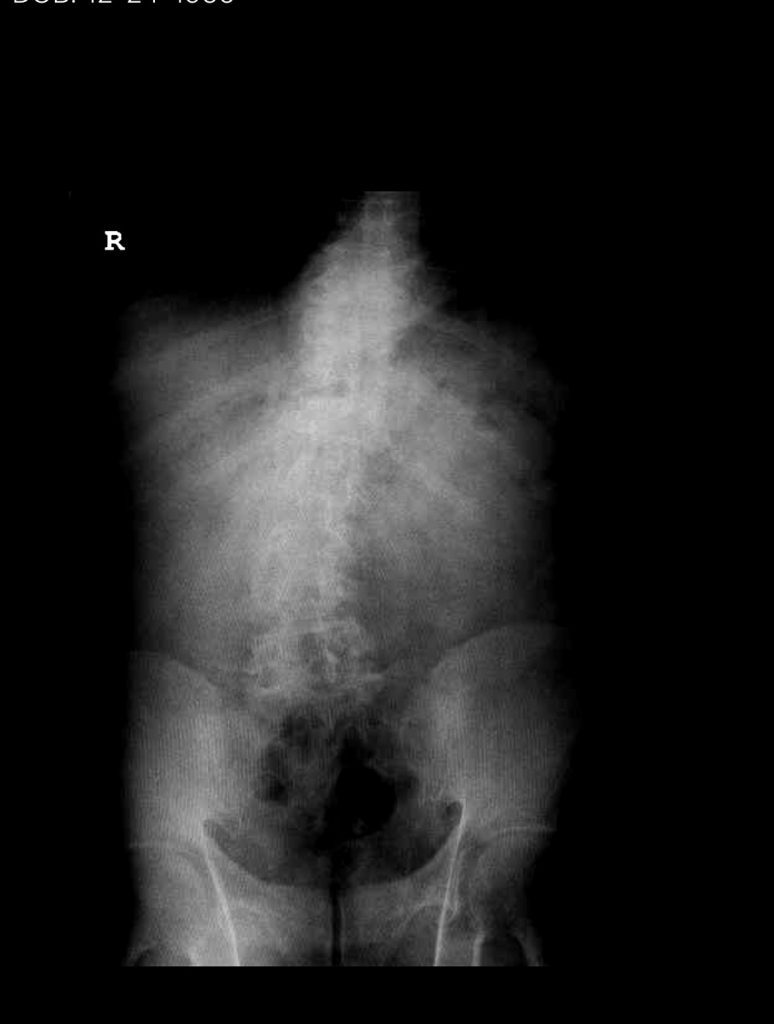

Figure 1. AP lumbar x-ray demonstrating degenerative lumbar levoscoliosis with secondary arthritic changes.

He had mild proximal weakness of his hip flexors.  He also had a history of diabetes, hypertension, and hypercholesterolemia. Imaging studies were obtained. Plain x-rays (Fig. 1) demonstrated a degenerative levoscoliosis with the apex of the curve at L2-3. Lumbar MRI (Fig. 2) showed severe degenerative disc disease with an L5-S1 grade 1 spondylolisthesis and a significant retrolisthesis at L3-4 with severe lumbar stenosis.